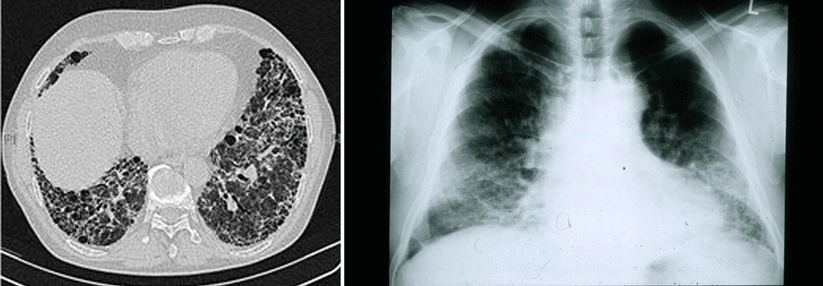

Beim metastasierten NSCLC sind Immuncheckpoint-Inhibitoren mit oder ohne Chemotherapie mittlerweile Standard, wie es auf der ESMO-Jahrestagung bestätigt wurde. Beim metastasierten NSCLC sind Immuncheckpoint-Inhibitoren mit oder ohne Chemotherapie mittlerweile Standard, wie es auf der ESMO-Jahrestagung bestätigt wurde. © WindyNight – stock.adobe.com

Immuncheckpoint-Inhibitoren mit oder ohne Chemotherapie sind mittlerweile Standard in der Erstlinienbehandlung des metastasierten NSCLC, das keine therapeutisch adressierbaren Treibermutationen aufweist. Auf der ESMO-Jahrestagung wurden 5-Jahres-Daten vorgestellt, die den Standard bestätigen. Neue Ergebnisse gab es auch zur Kombination aus Durvalumab und Tremelimumab.